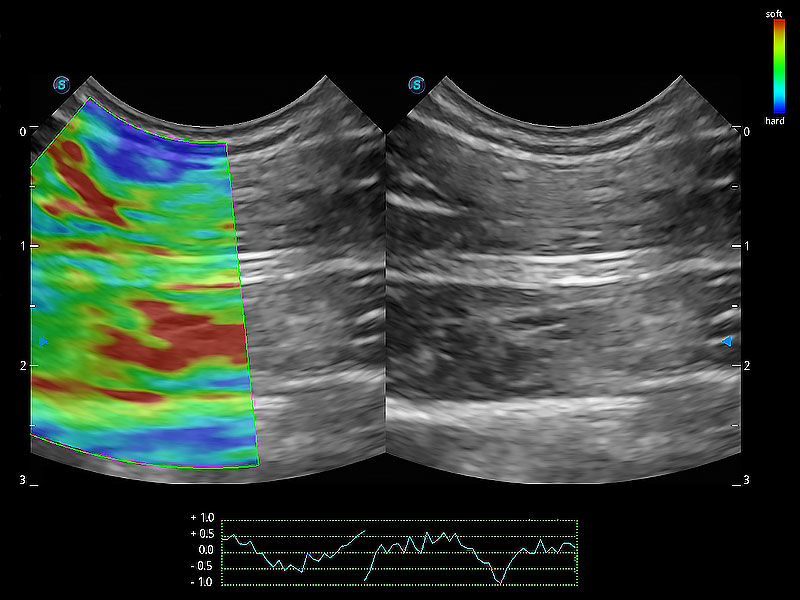

• 应变式弹性成像

操作简便,无需高频度外力作用即可真实反映组织的形变,快速评估肿瘤良恶性。

(犬)四腔心MQA